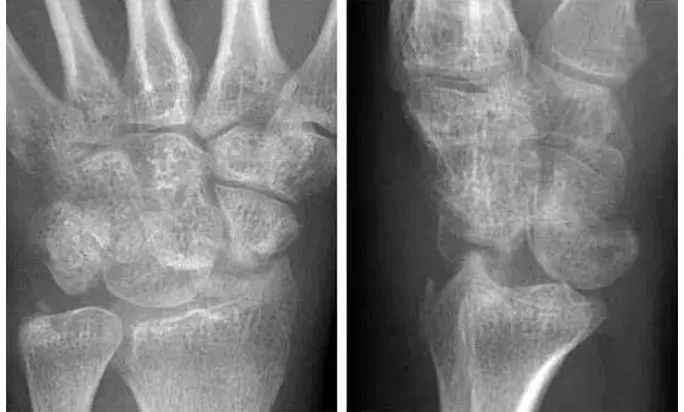

Case 分析

1.月骨-三角骨间隙不平行,存在重叠。

2.钩状骨和月骨也存在重叠。

3.桡骨、月骨、舟骨近极和头状骨近极平行关系存在。

4.三角骨、钩骨、头状骨远极、大多角骨和舟骨远极平行关系也存在。

5.头状骨和舟骨骨折。

诊断:经舟骨、经头状骨月骨周围骨折-脱位。